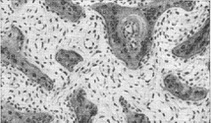

![]() Рис. 1. Остеокластическое розсмоктування компактного шару кістки. |

![]() Рис. 2. Розрісся эндост між примітивними кістковими балками. |

При мікроскопічному дослідженні наголошується перебудова кісткової тканини, що виражається в масивній остеокластичної резорбції кісткової речовини (рис. 1) в одних ділянках і новоутворенні його в інших. Найбільш активно ці процеси виражені в эндостальных відділах кісток, де відбувається розростання ендосту і освіта клітинно-волокнистої тканини, що заповнює кістковомозкові простору і нагадує фіброзну тканину. Ця тканина являє собою розрісся эндост і є остеогенної. У ній формуються комплекси нових кісткових балок (рис. 2). Останні в свою чергу також піддаються резорбції і замінюються новими, причому у зв'язку з бурхливими темпами процесу новоутворена кістка отримує примітивне будова, іноді вона не обызвествляется і тоді остеоидные балки і остеоидные зони виникають навколо старих балок.